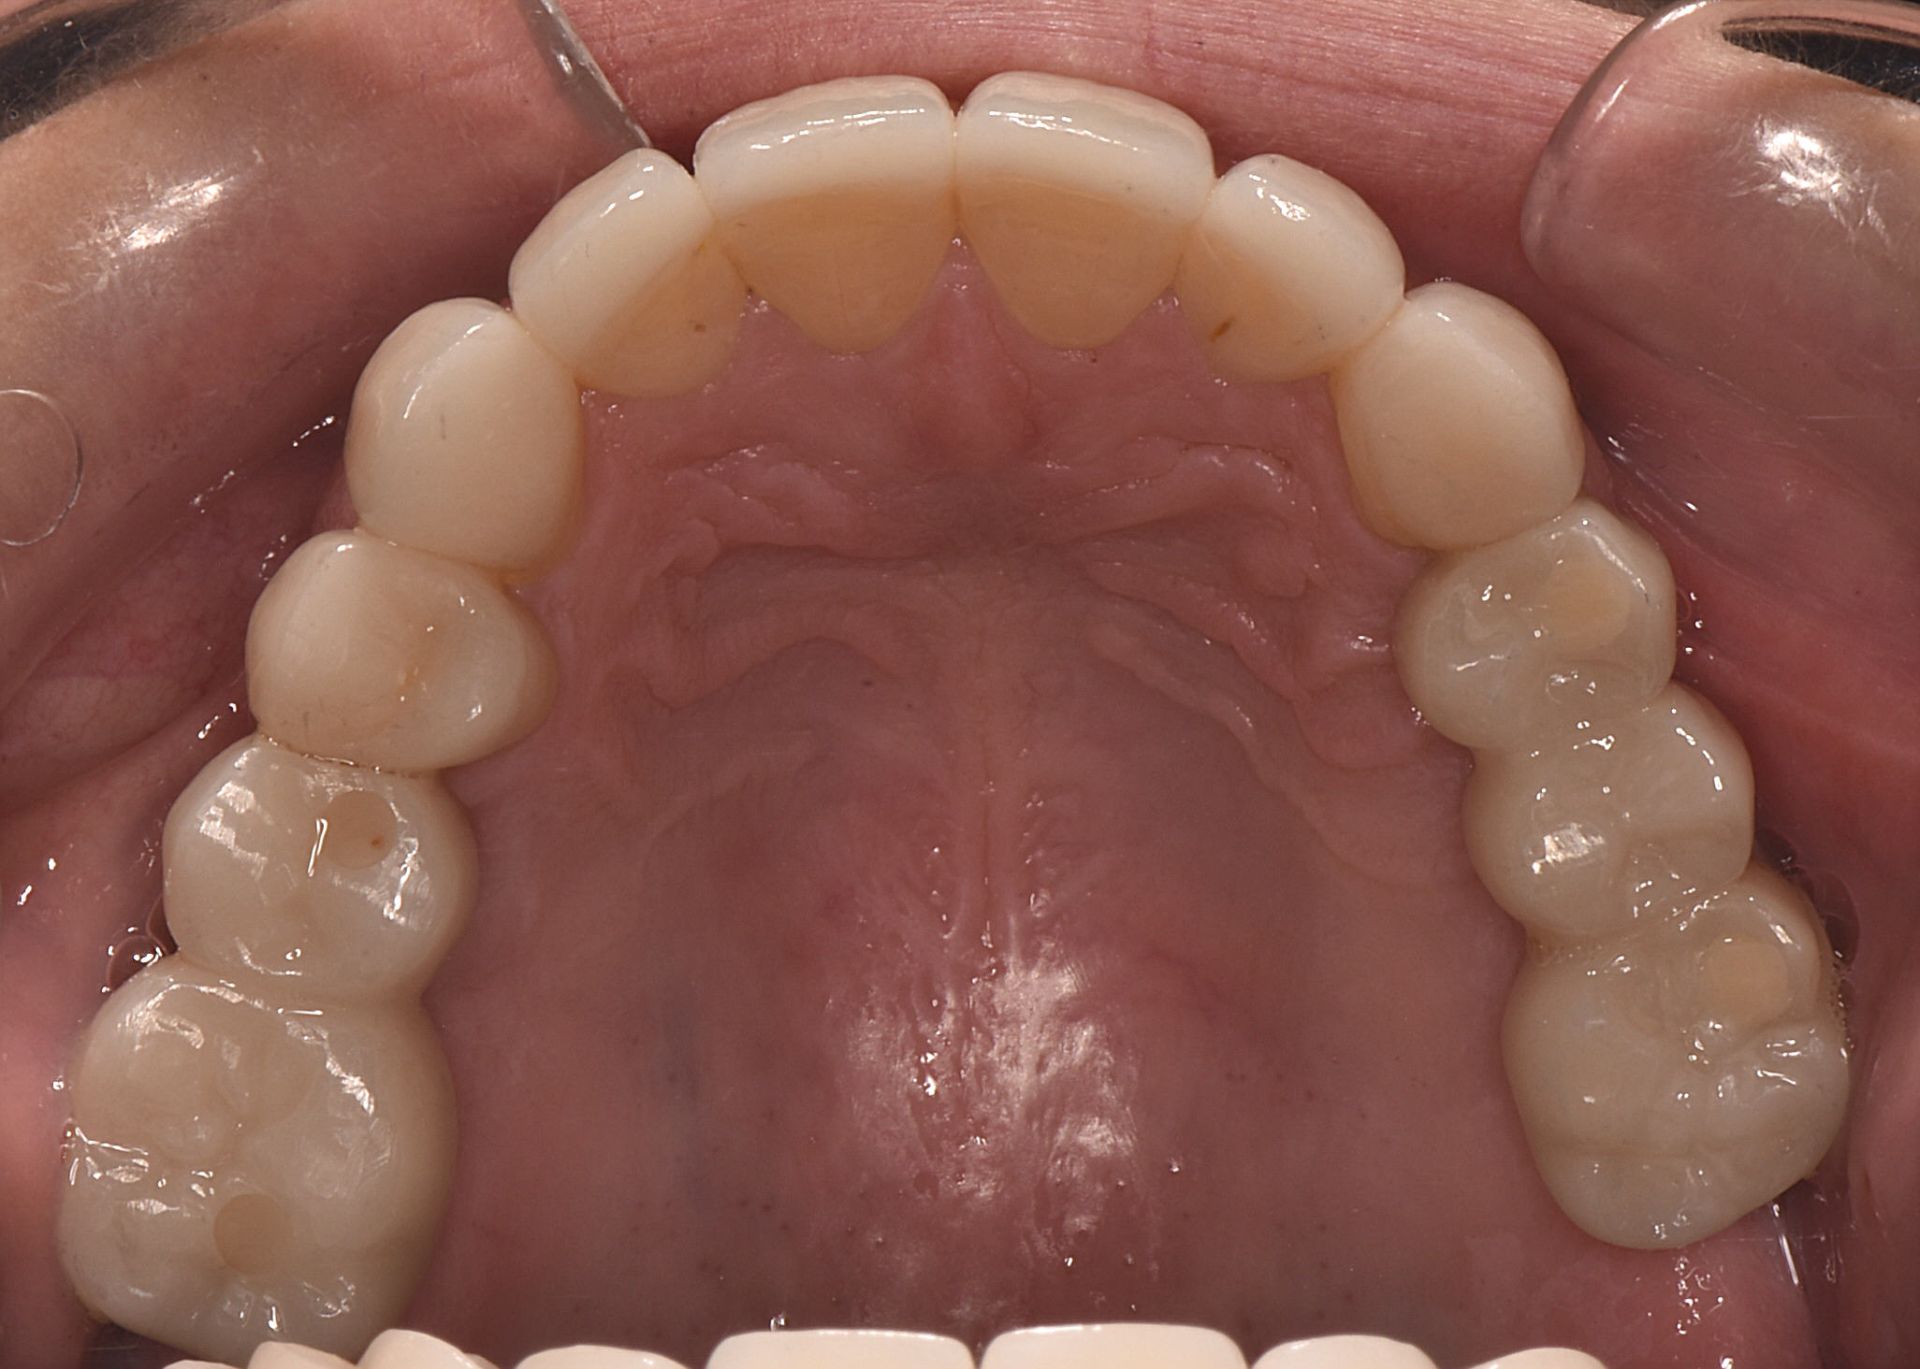

After